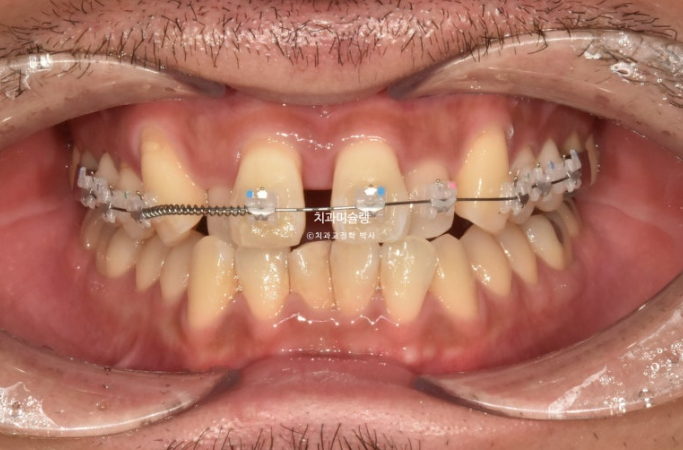

그 사이 윗니에 먼저 장치를 붙여 배열을 시작하고

24.12

2달 후 아랫니에도 장치를 붙여서 본격적인 교정을 시작합니다.